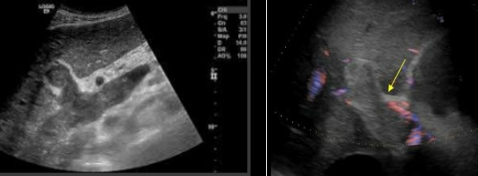

pyogenic abscess

ameobic abscess